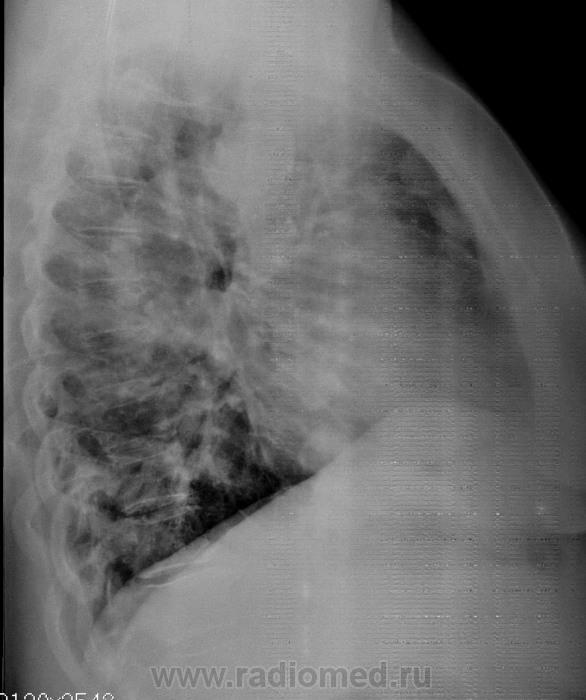

Метастазы откуда-то,Валентин Львович.Такое моё мнение.Круглые и много.Но все справа.

Слева во 2 м/р вроде есть

Откуда классика "стреляет".

3 года тому назад удалена (в ООД) матка и прочее, что рядом...